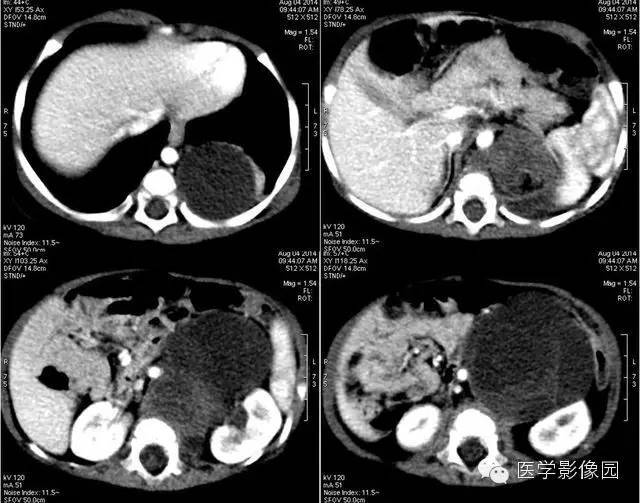

3——增强

4——增强

畸胎瘤是由两个或三个原始胚层组织演化而来的胚胎性肿瘤,大体上囊性、实性或囊实性兼有。囊性畸胎瘤又称皮样囊肿,仅含表皮及其附属成分,基本上均为良性。实性畸胎瘤含有三个胚层成分。按组织学分类可分为良性畸胎瘤和恶性畸胎瘤。良性畸胎瘤由分化良好的成熟组织构成,故又称为成熟畸胎瘤,瘤体囊性部分多于实质部分,小儿中绝大部分均为良性畸胎瘤。恶性畸胎瘤由胚胎发生时期的未成熟组织构成,实质部分常多于囊性部分,恶性畸胎瘤在小儿中十分少见。小儿畸胎瘤以女性多见,男女之比约为1:3-4,腹部包块和腹胀为腹膜后畸胎瘤主要的临床表现,患儿一般状况良好。

恶性畸胎瘤瘤体以实体为主,病变边界模糊不清,可侵犯周围组织,肿块大小对鉴别良恶性意义不大。